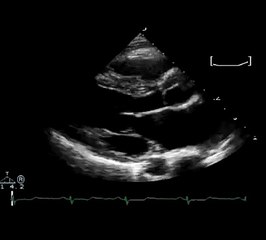

Mitral valve repair, which involved open heart surgery